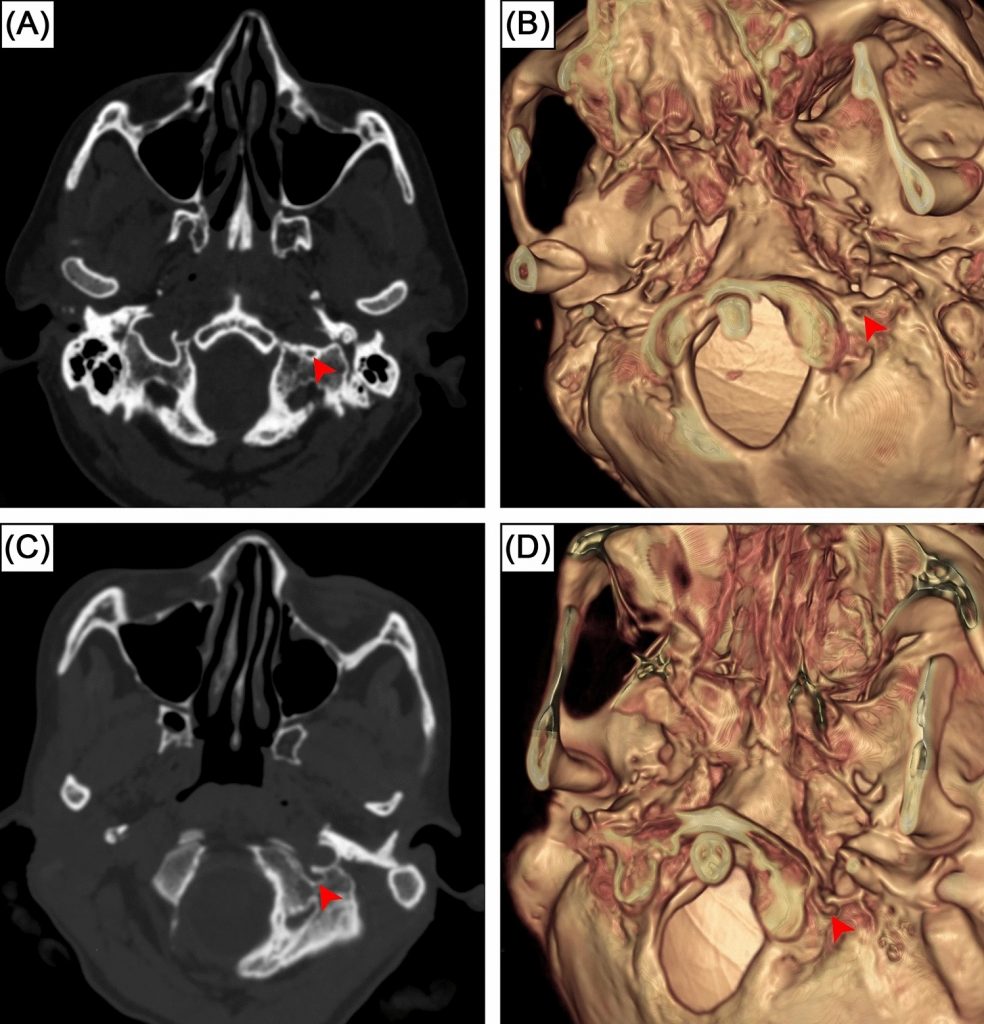

Intermediate condylar canal is a skull base canal in the condyloid fossa, located laterally to the occipital condyles and posteromedially to the jugular foramen. Despite its presence in the human skull base, this structure is rarely mentioned in textbooks and has not previously been examined radiologically. This study aimed to investigate the prevalence of intermediate condylar canal in CQ500 dataset, an open-access computed tomography scans of Indian population. A total of 490 head and neck computed tomography scans were thoroughly investigated. The presence of the intermediate condylar canal was investigated by two observers. Our results indicated the intermediate condylar canal was found in 10.5% of subjects (43 out of 410 individuals) or 6% of sides (49 out of 820 sides). Bilateral prevalence and unilateral prevalence were 1.5% (6 subjects) and 9% (37 subjects), respectively. No significant difference was found between sides. The width of these canals was 2.0 ± 0.5 mm (1.1–3.5 mm range). It is important to surgeons to be aware and familiar of intermediate condylar canal as it is located at the crucial crossroad of various surgical skull base approaches. This study serves as the fundamental research and further studies could include the investigation of intermediate condylar canal in skeletal specimens of various ethnic origins and imaging study to examine the content of the canals.